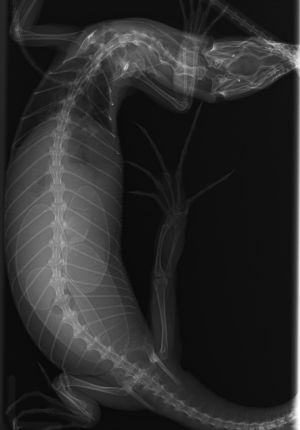

コルデンシスツリーモニターの卵塞・腸重積

今回は卵が腸管に逆流してしまい、それが原因で腸重積(腸の一部が隣の腸の中に入り込んでしまう状態)を起こしてしまったツリーモニターさんのご紹介です。※ちなみにこの子は、院長が獣医師になった年から一緒に過ごしている子であり、ホームページの宣材写真にも一緒に写っている子です。本当に助かって良かった...

すると4つあった卵が1つに減っていました。超音波検査では萎んだ卵のようなものがもう一つ確認できたので、卵詰まりの可能性を考え手術を行いました。

全身麻酔をかけてお腹を開くと、卵管の中には綺麗な卵が1つ見つかりました。

他の卵を探すと、なんと腸管の中に萎んだ卵のようなものが入っており、その部分の腸管は重責を起こしていました。

幸い、腸管の炎症は軽度で、手で重責を整復した後萎んだ卵はお尻から出すことが出来ました。

爬虫類さんは総排泄孔という1つの穴から産卵も排尿も排泄も行うため、何らかの原因で迷入してしまったのだと推察されます。